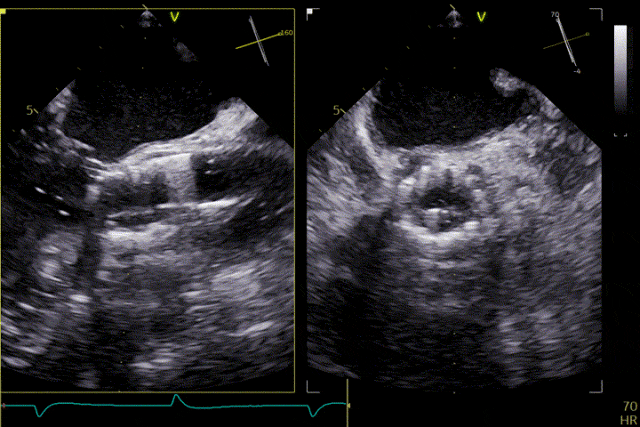

打開定位件

定位件入竇

瓣膜釋放

患者主動脈瓣重度反流得到糾正,術後無反流、無瓣周漏。術後心臟超聲顯示人工生物瓣啟閉功能良好,平均跨瓣壓差2 mmHg,血流速度正常。患者恢復情況良好,心功能較術前明顯改善。